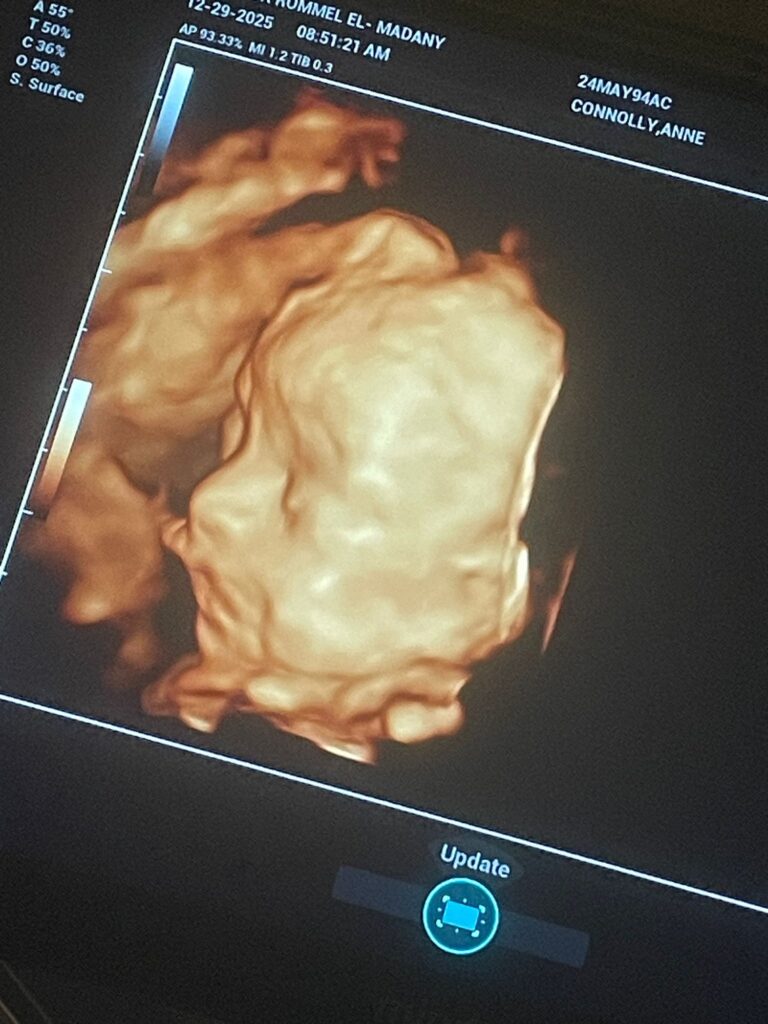

Up until that point, pregnancy still felt abstract. But hearing that tiny heartbeat made it real. There was actually a little person in there. From that moment, I started thinking about her differently. I would catch myself wondering what she would look like, what kind of personality she might have, and what life would look like once she arrived.

Pregnancy itself had a lot of ups and downs. There were doctor visits, tests, and moments where things were uncertain. I realized quickly that pregnancy is a lot of waiting and a lot of hoping that everything continues progressing normally.